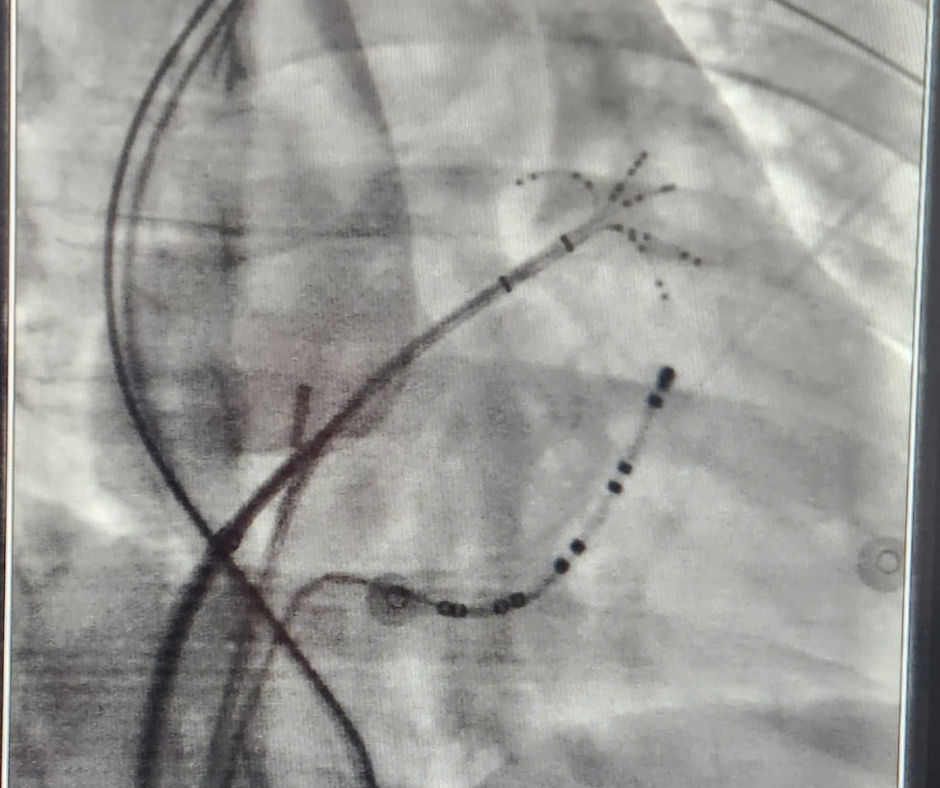

EsoSure, estilete de nitinol que es flexible a temperatura ambiente para una colocación en el lumen de un salem de 18 Fr dentro de la sonda orogástrica y asume una firme curva en forma de S a temperatura corporal para crear una deflexión esofágica.

Un producto único para brindar seguridad en el momento de los procedimientos de Ablación de la Fibrilación Auricular.